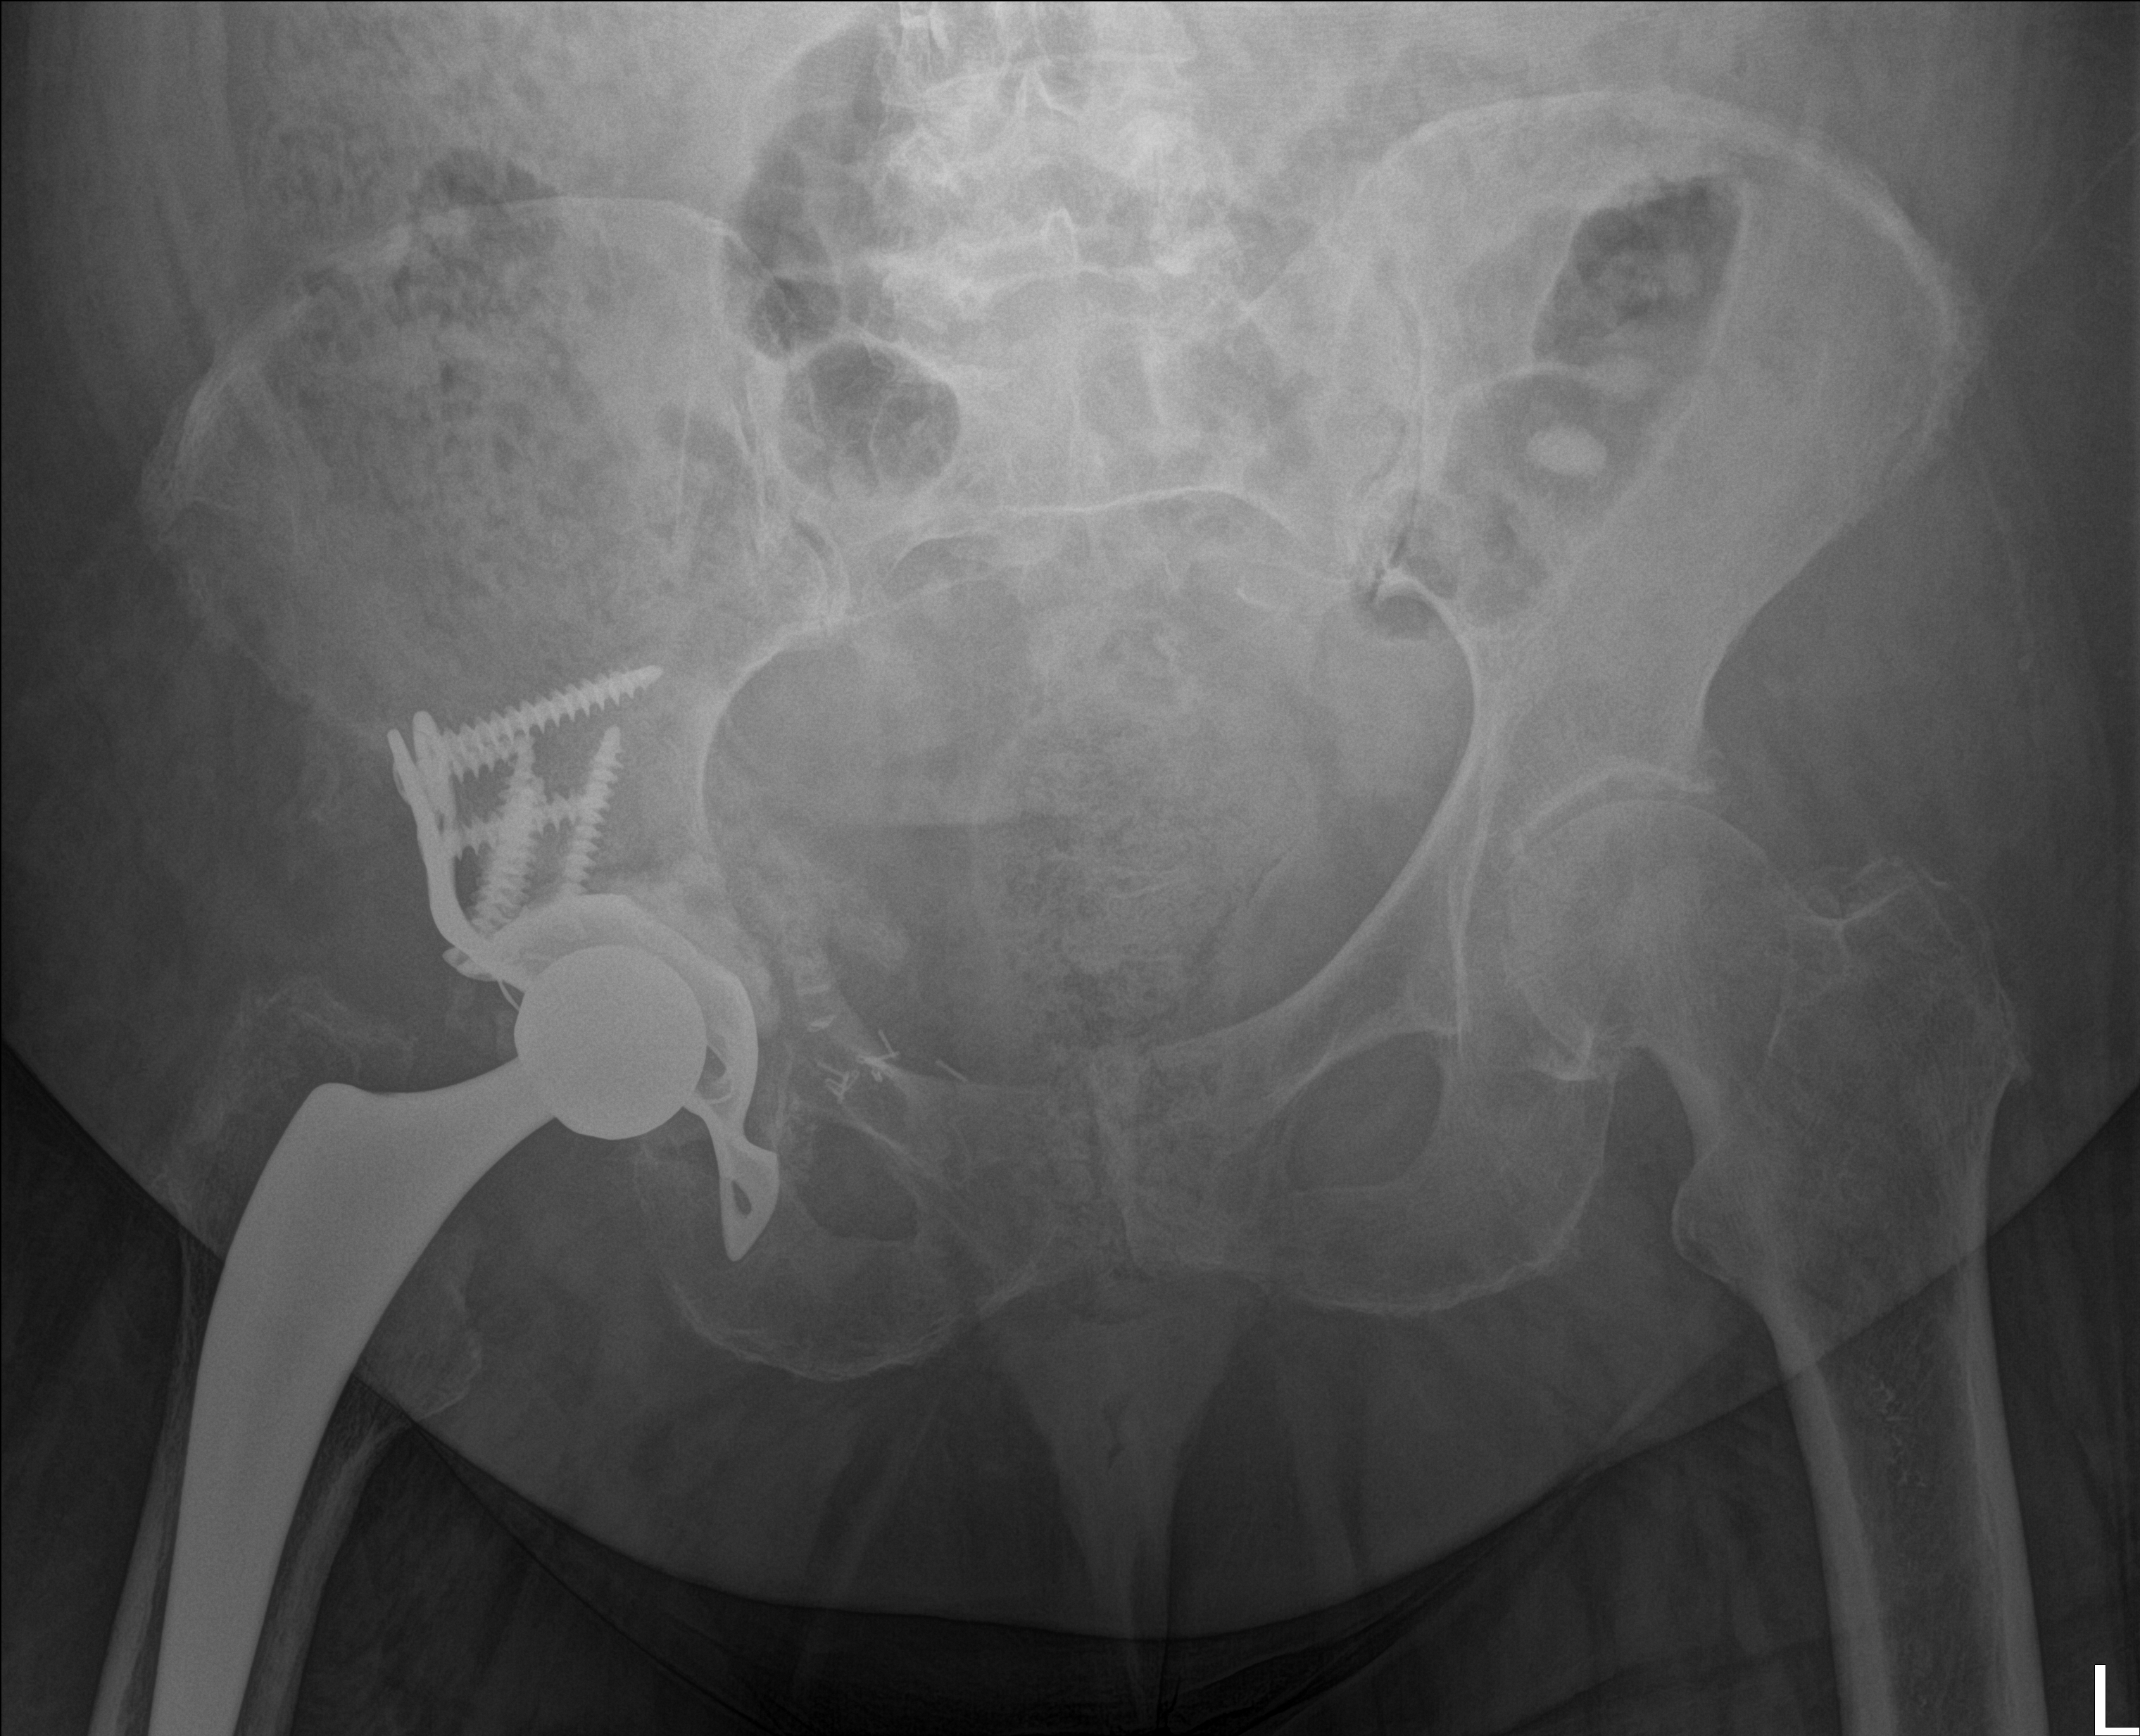

Akuter Befund: Hüftprothesen-Luxation

Vergleich der Röntgenbilder zeigt eine Luxation der Hüft-TEP rechts. Der Prothesenkopf ist aus der Pfanne ausgerenkt.

21.11.2025 - Luxation!

Becken 2025

Prothesenkopf luxiert nach medial/kaudal

Verlauf: Die Luxation/Pfannendislokation führte zur stationären Aufnahme im Universitätsklinikum Heidelberg (28.12.2025). Am 30.12.2025 wurde die TEP entfernt und ein Spacer implantiert. Infektnachweis: Enterococcus faecalis. Am 19.02.2026 wurde die neue Prothese erfolgreich eingebaut (stationär bis 05.03.2026). Komplikationsloser Verlauf, regelrechte Implantatlage im Röntgen. Entlassung mit 20kg Teillast, Amoxicillin für 6 Wochen. Wiedervorstellung am 09.04.2026.

21.11.2025

Röntgen Becken + Hüfte rechts

2 Aufnahmen | 2836x2336 px | 4.3 MB

November 2025

Aktuelle Röntgenbilder + Labor

Röntgen Becken und Hüfte rechts mit Radiologiebefunden, Laborbefund und Arztbericht

Röntgen Becken

DICOM

Luxation der Hüft-TEP